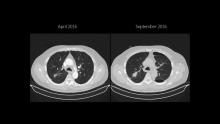

As the RUL was initially accessible for a wedge resection, the LLL nodule was approached first. A non-intubated SI-VATS S6 LLL anatomical segmentectomy was performed in April 2016. Four months later, a segmental S6 bronchopleural fistula was diagnosed and successfully managed with an endobronchial valve. A new chest scan then showed growth of the RUL lesion, requiring a posterior S2 segmentectomy instead of the initial wedge planned (Figure 1).

Figure 1